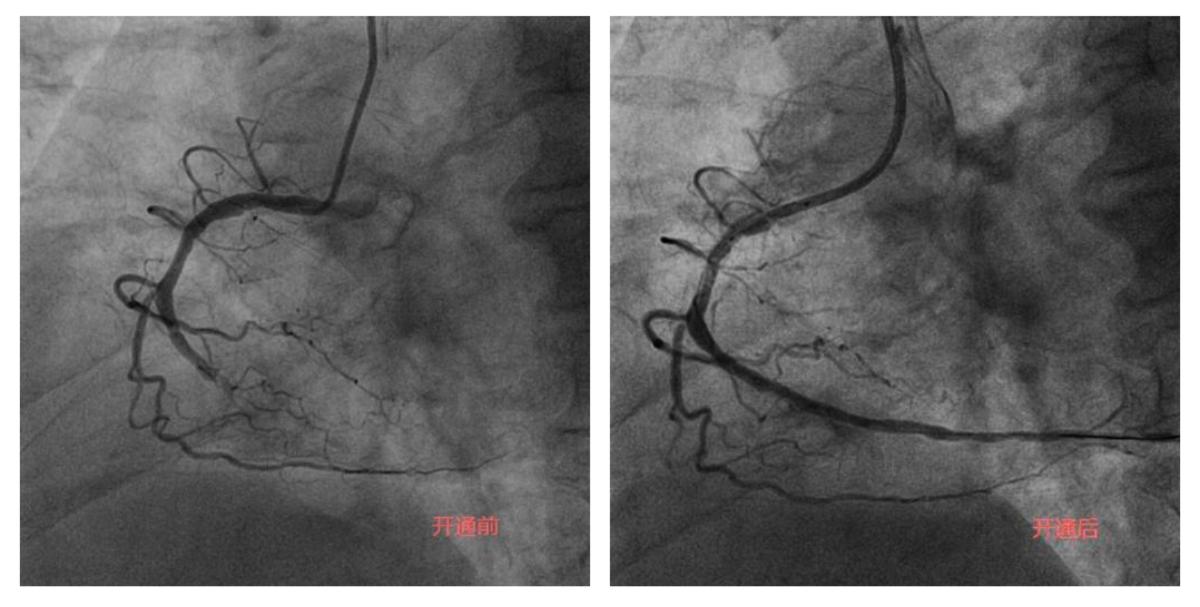

李奶奶今年92岁高龄,两年前曾因“急性心肌梗死”就诊于某医院,接诊专家考虑患者年龄大,合并症多,冠状动脉介入操作风险高,建议药物治疗。近半个月以来,李奶奶的胸痛症状频繁发作,药物治疗效果不佳,经过病友的介绍,家属选择了附属潞河医院翟光耀主任团队。在心脏监护室医护人员的精心治疗和护理下,李奶奶心功能改善,肺部感染得到控制,可以耐受手术。术中,冠状动脉造影显示LAD弥漫重度狭窄,RCA完全闭塞伴重度钙化。在经过近两个小时的不断尝试及努力后,闭塞的RCA成功开通,“介入无植入”未植入支架,血管成功修复。术后李奶奶恢复良好,顺利出院。